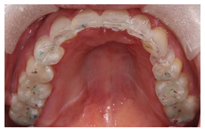

垫,口内戴入透明

垫后与

架上咬合一致,正中咬合时后牙功能尖多点接触,前牙轻接触,侧方运动时右侧尖牙引导,左侧23、24、25组牙引导。嘱患者发S音,评估前牙的位置及垂直距离,发F音和V音,评价切牙的长度和形状(图17,图18,图19,图20,图21,图22,图23)。